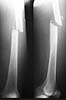

Here are the post op pictures.

To recap: Middle aged male patient on whom a heavy log fell and sustained injury. Had pelvic ring disruption with fracture femur. Ext fix of pelvis and interlocking nailing of femur done. Developed compartment syndrome thigh and had fasciotomy. Went on to rhabdomyolysis and ARDS. Managed with ventillation and alkalinising. Fasciotomy wound later skin grafted.

Now what I have not told so far: At about three weeks after the injury when patient had recovered from the problems described above developed acalculous cholecystitis. As he was being prepared for surgery he suddenely collapsed and went into shock. Required resuscitation and inotropic support. After vital signs were stable he was taken up for laparoscopic cholecystectomy. On introducing the scope it was found that there was a gangrenous gall bladder with lots of inflammation all around. It was converted to an open cholecystectomy. Ventillated post op. Patient's ext fix on pelvis was removed after six weeks and ambulated with walker. Had developed a deep sacral pressure sore. Discharged with home care of pressure sore and ambulation with support. Now at about three weeks the femur is uniting, pelvis stable and the pressure sore healing. Patient changed to axillary crutches from walker.